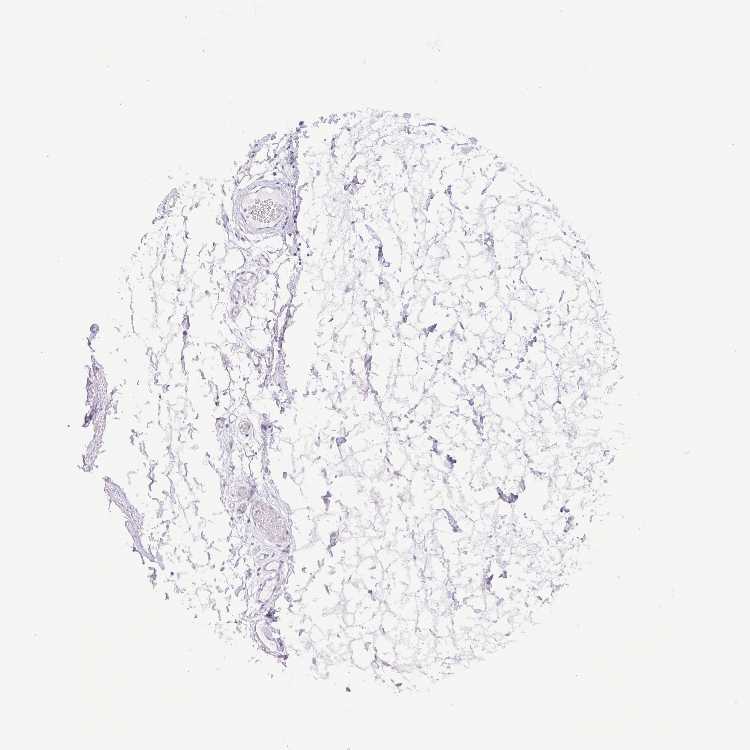

TISSUE PRIMARY DATA ADIPOSE TISSUE Show tissue menu

ADIPOSE TISSUE - Expression summary

ADIPOSE TISSUE - Antibody stainingi

Antibody staining in the annotated cell types in the current human tissue is reported as not detected, low, medium, or high, based on conventional immunohistochemistry profiling in selected tissues. This score is based on the combination of the staining intensity and fraction of stained cells.

Each image is clickable and will lead to virtual microscopy that enables deeper exploration of all samples and also displays staining intensity scores, fraction scores and subcellular localization as well as patient and tissue information for each sample.

Antibody HPA013331Antibody HPA039262Antibody CAB033884

Adipocytes Not detectedNot detectedNot detected